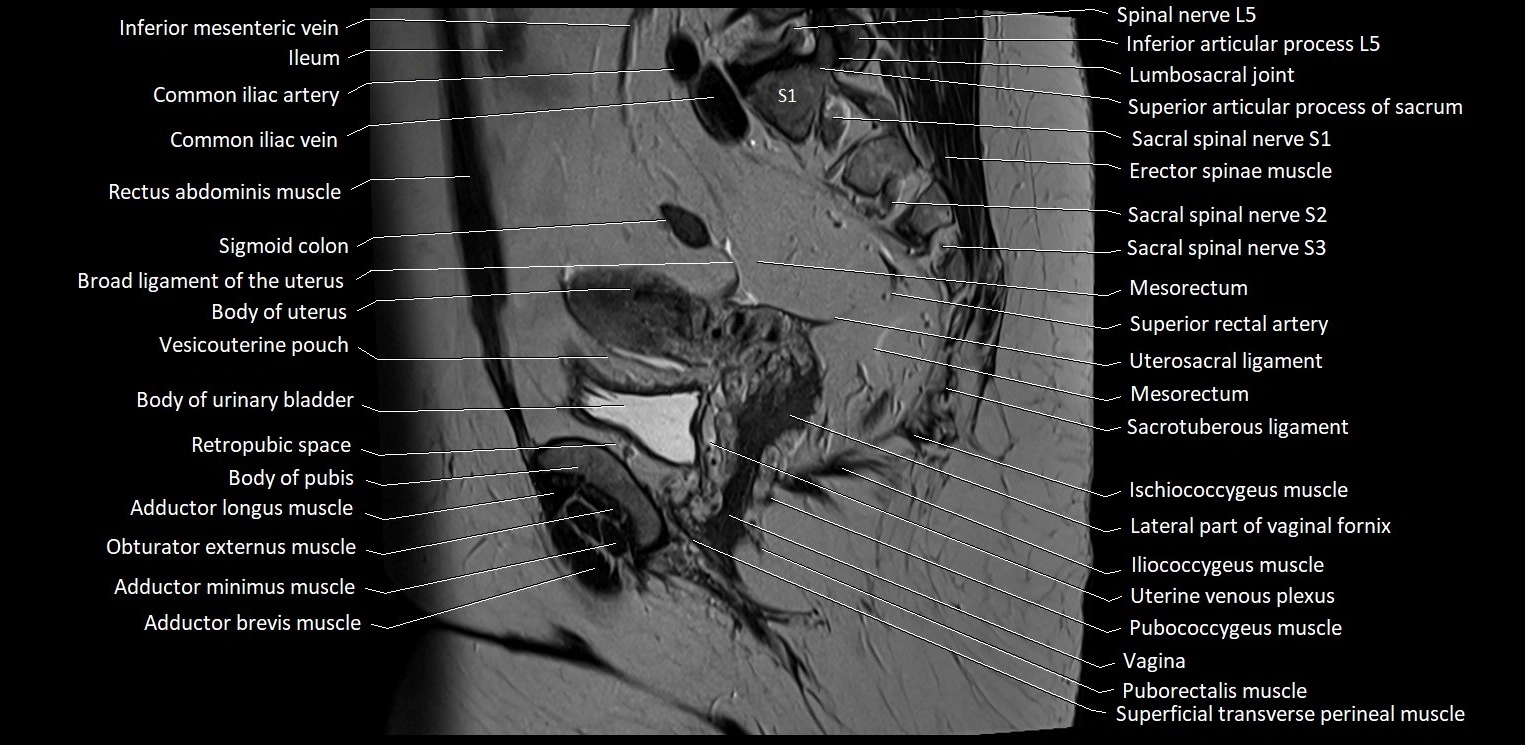

- Body of urinary bladder

- Body of uterus

- Broad ligament of uterus

- Common iliac vein

- Ileum

- Iliococcygeus muscle

- Inferior articular process of L5 vertebra

- Inferior mesenteric vein

- Internal iliac artery

- Ischiococcygeus muscle

- Lumbosacral joint

- Mesorectal fascia

- Mesorectum

- Pubococcygeus muscle

- Puborectalis muscle

- Rectouterine pouch (pouch of Douglas)

- Retropubic space

- Sacrotuberous ligament

- Sigmoid colon

- Spinal nerve L5

- Spinal nerve S1

- Spinal nerve S2

- Spinal nerve S3

- Superficial transverse perineal muscle

- Superior articular process of S1 vertebra

- Superior articular process of sacrum

- Superior rectal artery

- Uterosacral ligament

- Vagina

- Vesicouterine pouch